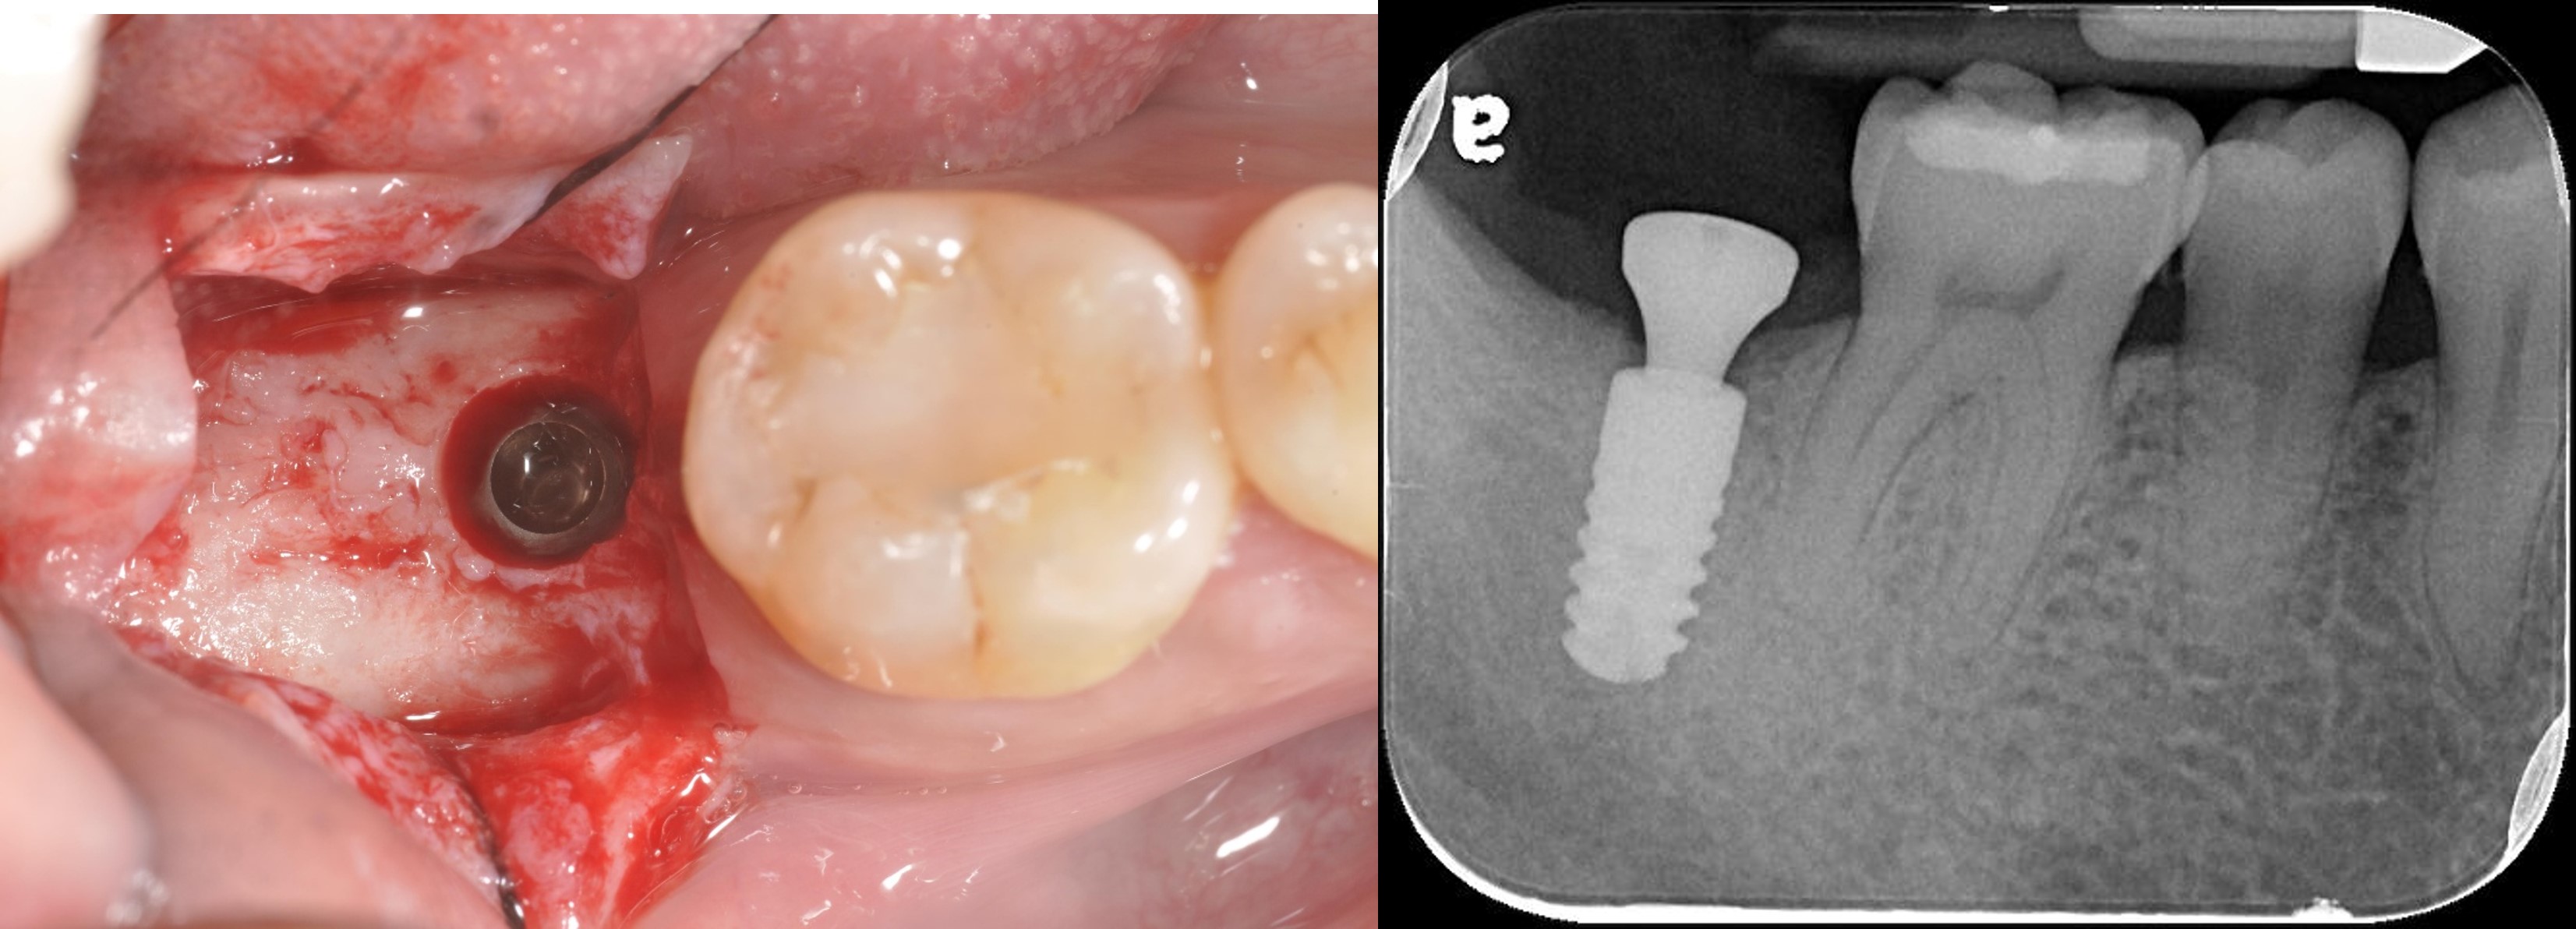

拔牙後進行骨脊保存術

植牙